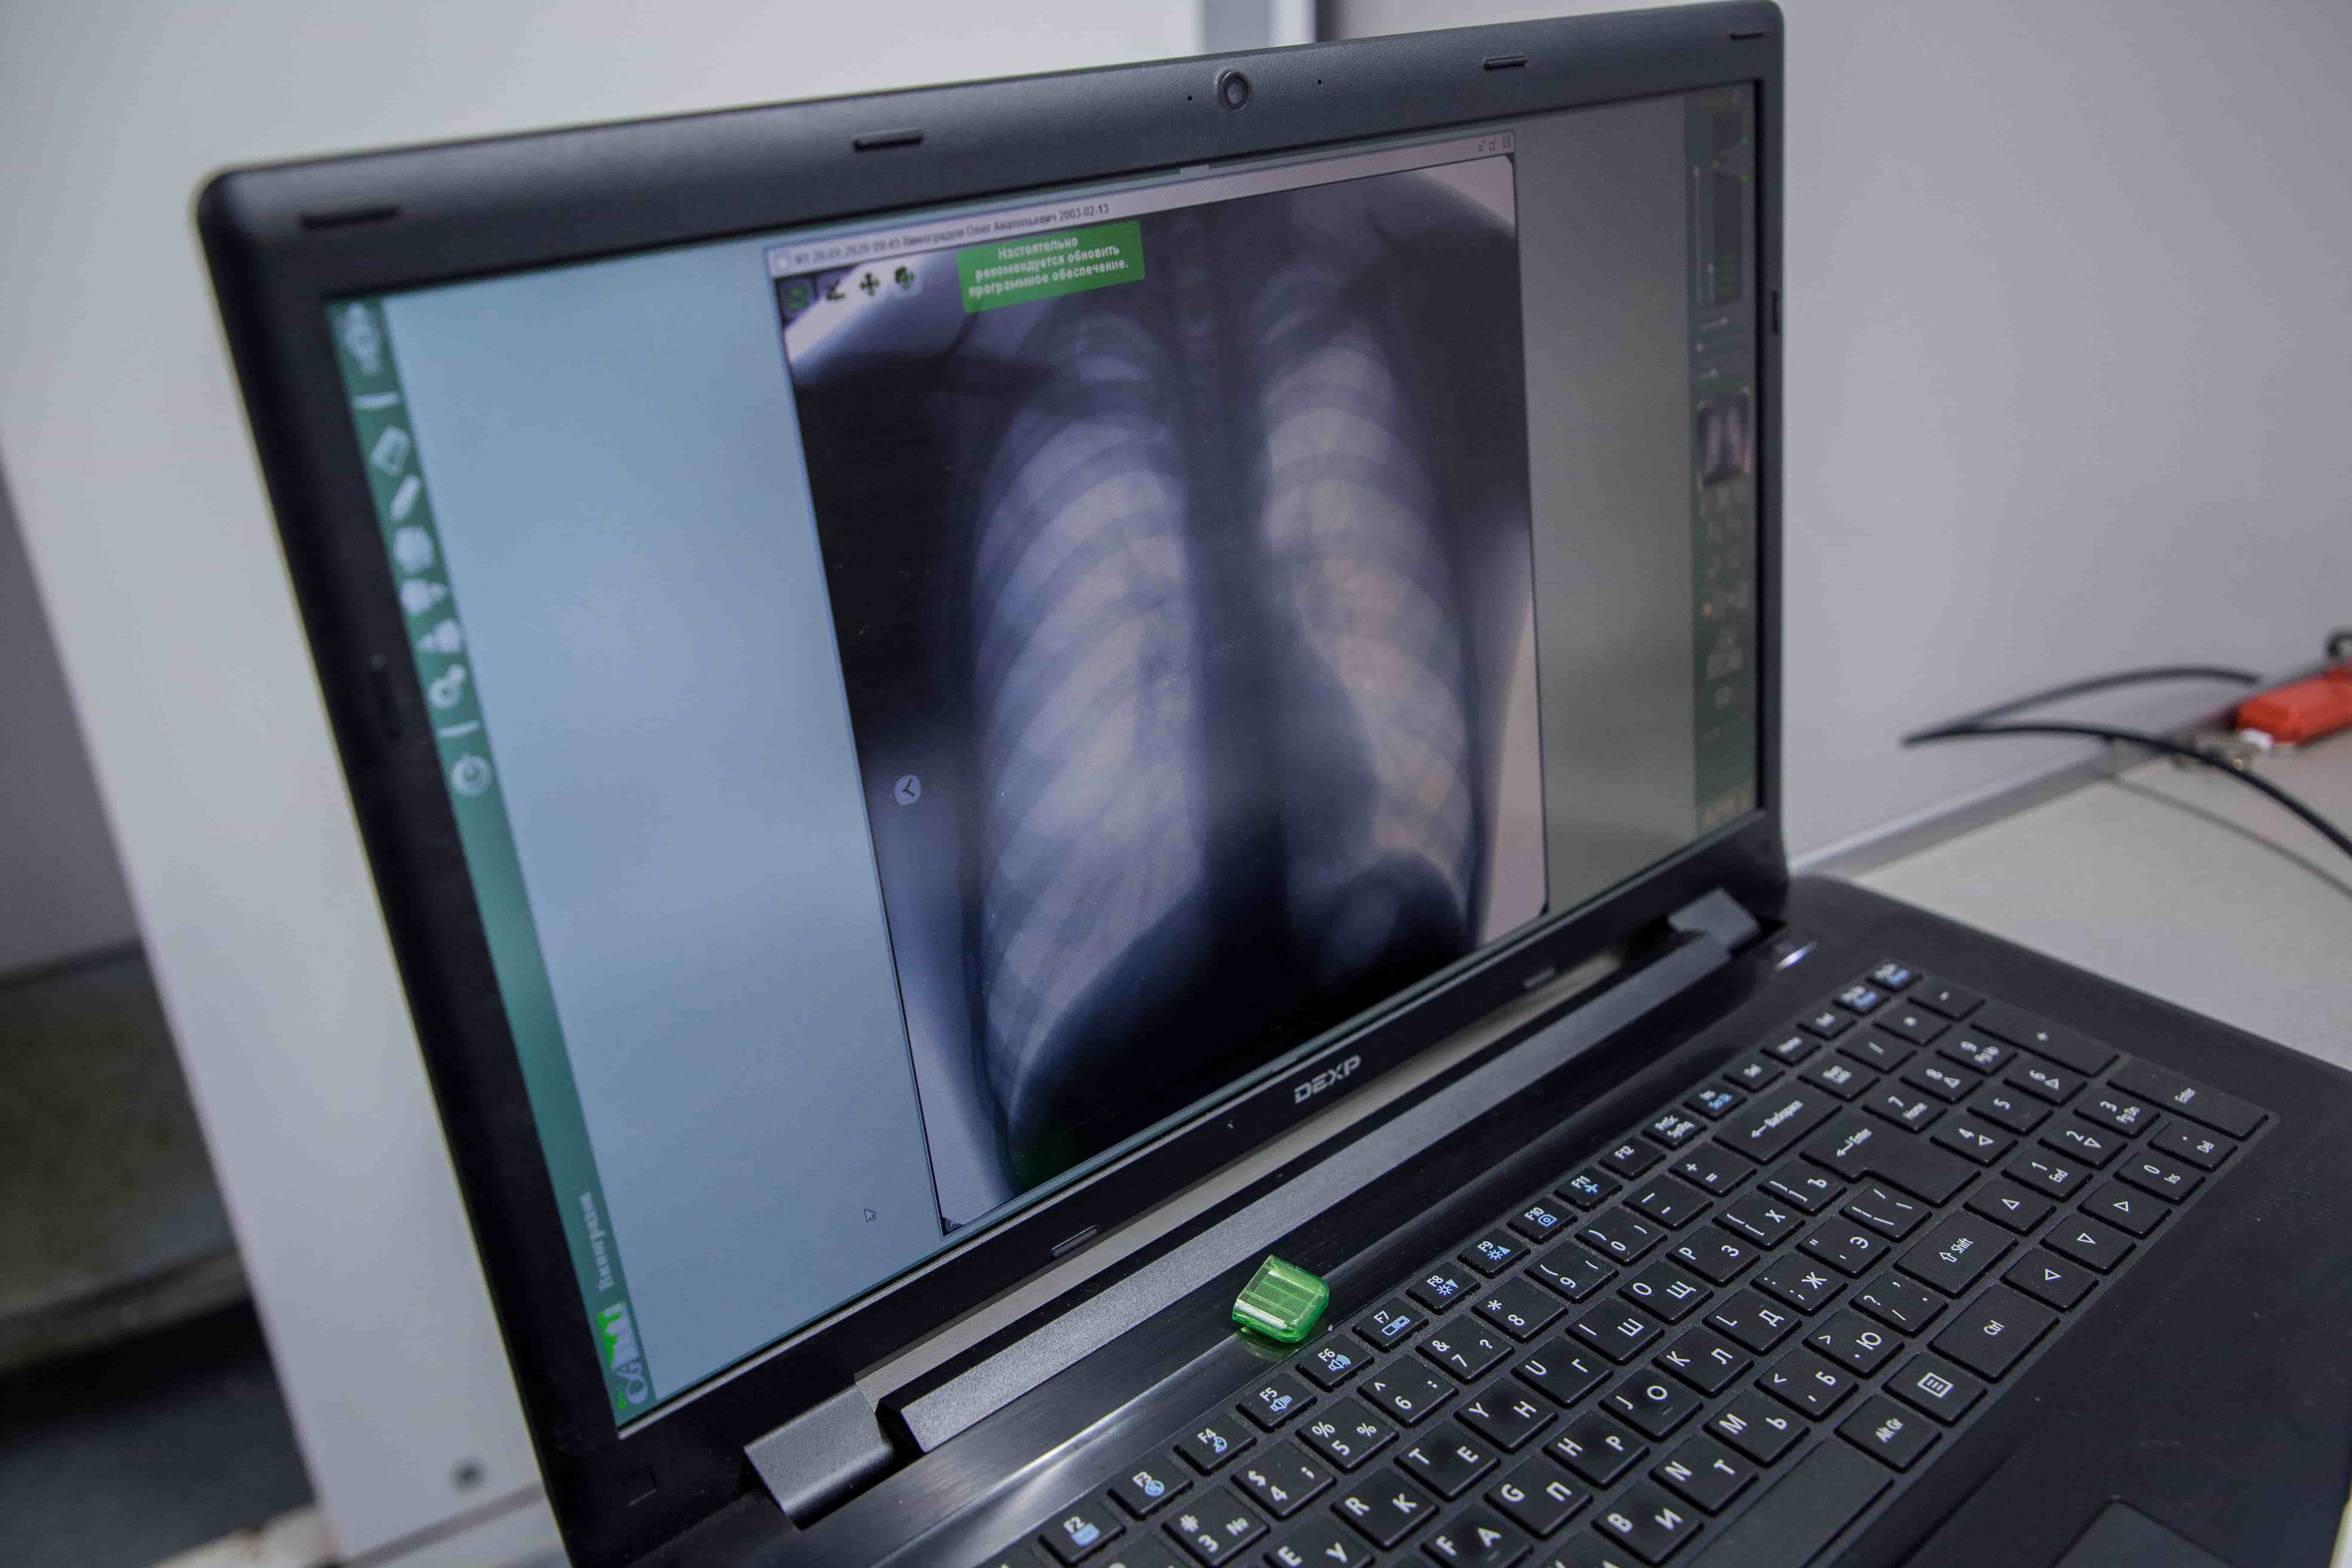

Туберкулез продолжает оставаться достаточно распространенным и трудно излечимым заболеванием, которое чаще всего клинически никак не проявляется. Поэтому профилактические мероприятия – это необходимость. У детей это реакция Манту и диаскинтест, у взрослых – флюорографическое обследование.

Напомним, что флюорографическое обследование необходимо проходить один раз в год. Лучевая нагрузка при этом на организм человека минимальная, сравнимая с нахождением перед компьютером в течение дня.